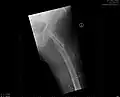

So genannte nichtdislozierte (also unverschobene) bzw. eingestauchte mediale Schenkelhalsfrakturen mit flachem Frakturneigungswinkel werden häufig mittels so genannter Zugschrauben behandelt (siehe Abbildung). Es handelt sich um hohle Schrauben, die über zuvor eingebrachte Führungsdrähte geschraubt werden (Lochschrauben). Bei jüngeren Patienten versucht man in der Regel, den Oberschenkelkopf zu erhalten. Auch hierzu werden Schrauben verwendet.[12]

- Zugschraubenosteosynthese bei einer medialen Fraktur. Behandlung einer nicht dislozierten medialen Schenkelhalsfraktur bei einer 92-jährigen Patientin.

Aufnahme vor der OP. a.p.-Aufnahme. Die Fraktur ist mit einem Pfeil markiert. -

Seitliche Aufnahme. Die Fraktur ist mit einem Pfeil markiert. -

Nach OP mit Zugschrauben, a.p.-Aufnahme. Man sieht die noch liegende Redondrainage. -

Seitliche Aufnahme.